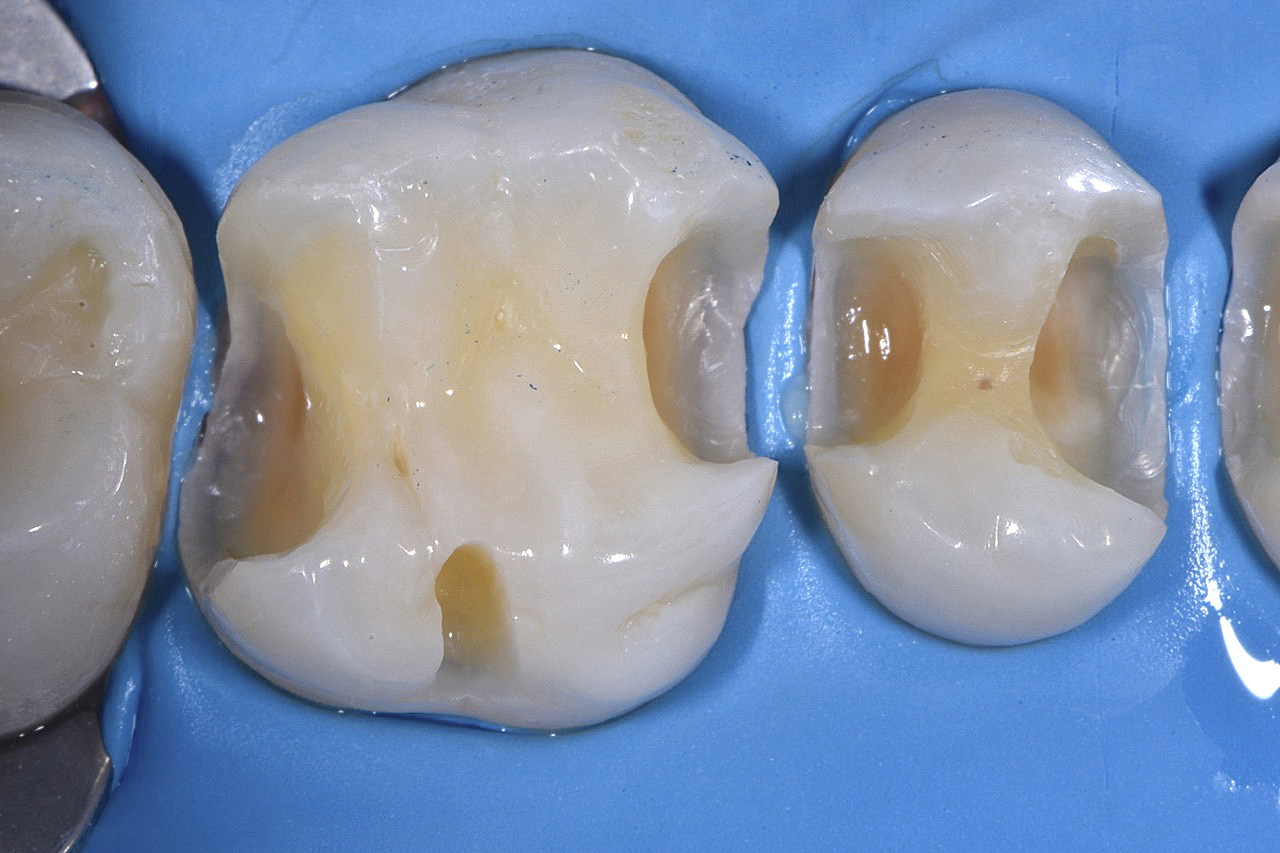

Vengono utilizzati 2 tipi di provvisori: il primo, cementato ai denti vicini, viene utilizzato dal momento dell’estrazione del dente fino ad impianto osteointegrato (circa 6 mesi); il secondo, avvitato direttamente all’impianto, ha una funzione di prova estetica ma soprattutto di guida per la maturazione dei tessuti gengivali peri-implantari portandoli verso la maturazione completa prima di posizionare la corona finale in disilicato di litio.